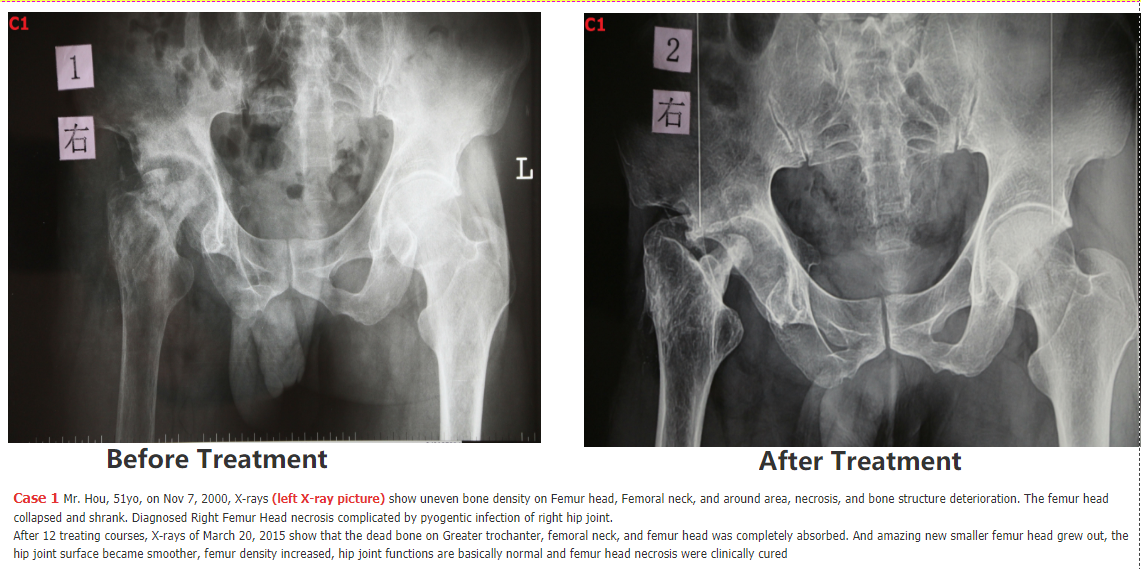

5. following are SOME Chinese patients we have cured - we will add the cases 5, 6, 7, 8, 9, 10, 11, 12.... SOON